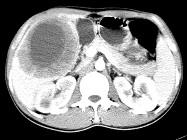

问题 女,61岁,上腹部疼痛1个月,食欲减退,消瘦,CT所见如图,最可能的诊断是()

选项 A.肝脓肿 B.肝转移瘤 C.胃癌肝转移 D.肝包虫病 E.原发性肝癌

答案 C